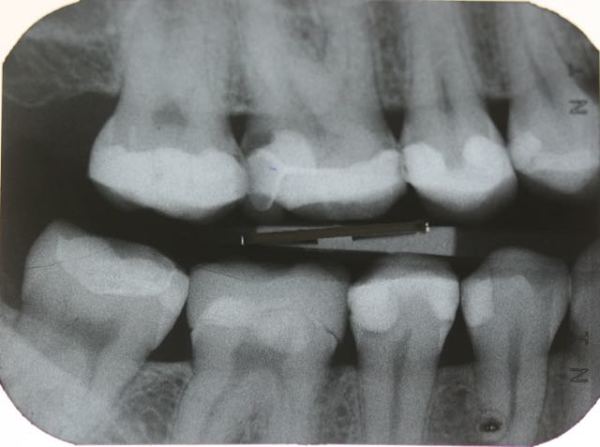

Der nächste Schritt nach der Entfernung der Karies ist in jedem Fall die Aufbaufüllung. Beide Zähne erhalten Retraktionsfäden und werden mit einem chemisch härtenden Aufbaumaterial ausgespritzt und dann fix und fertig zur Aufnahme der Kronen präpariert. Die Behandlungssitzung endet mit der provisorischen Versorgung.